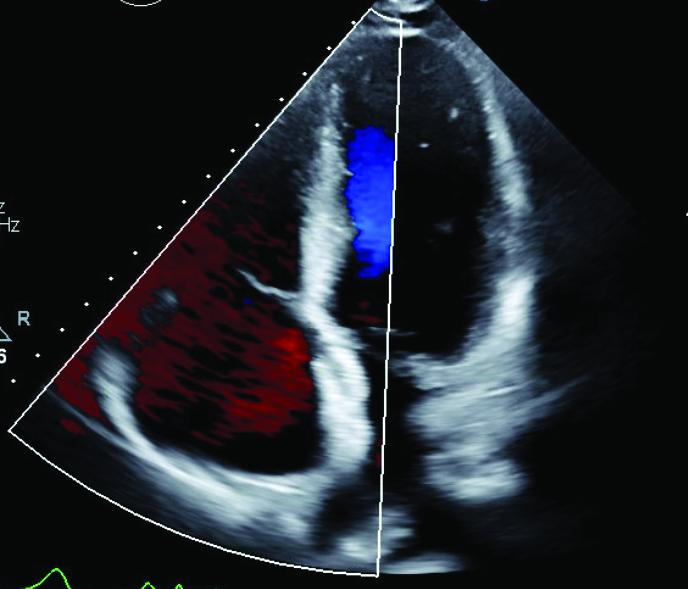

Further workup included a TTE that showed no acute abnormality and a stable pulmonic valve without any signs of insufficiency. But shunting was suspected, and a bubble study showed a secundum ASD with large right to left shunt (Figure 3). A transesophageal echocardiogram (TEE) showed only trace tricuspid regurgitation and a large fenestrated ostium secundum ASD with bidirectional shunt (Figure 4).

Figure 4

Figure 4. Transesophageal echocardiogram color Doppler displaying shunting through 1.6 cm ostium secundum atrial septal defect with superior fenestration.